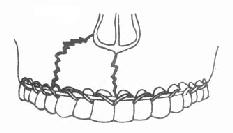

1.单颌牙弓夹板固定法:是用直径2毫米的铝丝或成品带钩牙弓夹板,按牙弓形态成形,然后用较细的金属结扎丝穿过牙间隙,将牙弓夹板结扎在骨折线两侧的部分或全部牙齿上(图4-18),以固定骨折段。这种方法适用于无明显移位的骨折,如下颌骨颏部正中线性骨折、局限性牙槽突骨折。

| 图4-18 单颌牙弓夹板固定 | 图4-19 颌间牵引固定法 |